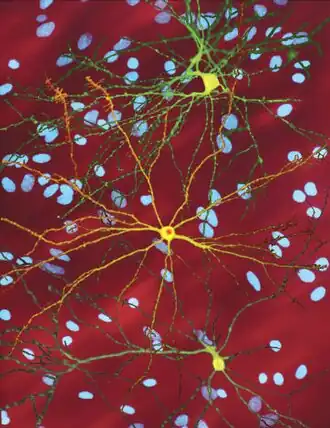

Initially, damage to the brain is regionally specific with the dorsal striatum in the subcortical basal ganglia being primarily affected, followed later by cortical involvement in all areas.[58][59] Other areas of the basal ganglia affected include the substantia nigra; cortical involvement includes cortical layers 3, 5, and 6; also evident is involvement of the hippocampus, Purkinje cells in the cerebellum, lateral tuberal nuclei of the hypothalamus and parts of the thalamus.[29] These areas are affected according to their structure and the types of neurons they contain, reducing in size as they lose cells.[29] Striatal medium spiny neurons are the most vulnerable, particularly ones with projections towards the external globus pallidus, with interneurons and spiny cells projecting to the internal globus pallidus being less affected.[29][60] HD also causes an abnormal increase in astrocytes and activation of the brain's immune cells, microglia.[61]